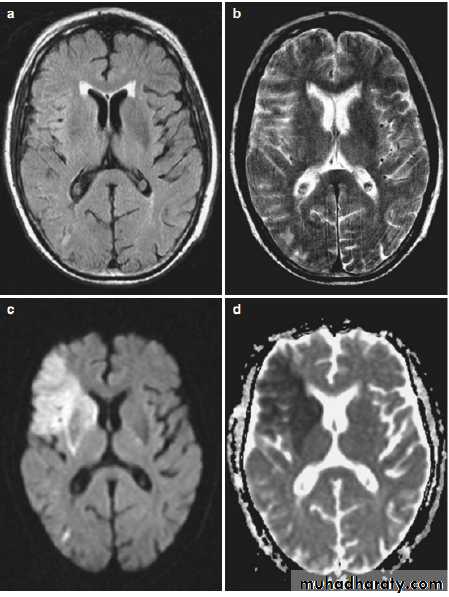

Functional MRI sequences

• Diffusion-weighted imaging (DWI) is sensitive to the random Brownian motion (diffusion) of water molecules within tissue. The greater the amount of diffusion, the greater the signal loss on DWI. Areas of reduced water molecule diffusion show on DWI as relatively high signal. Diffusion-weighted imaging is the most sensitive imaging test available for the diagnosis of acute cerebral infarction, epidermoid cyst and abscess.• Perfusion-weighted imaging (PWI) may be used in patients with cerebral infarct to map out areas of brain at risk of ischemia that may be salvageable with thrombolysis.